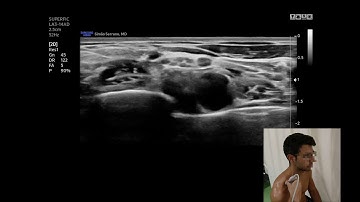

Suprascapular nerve block - distal approach